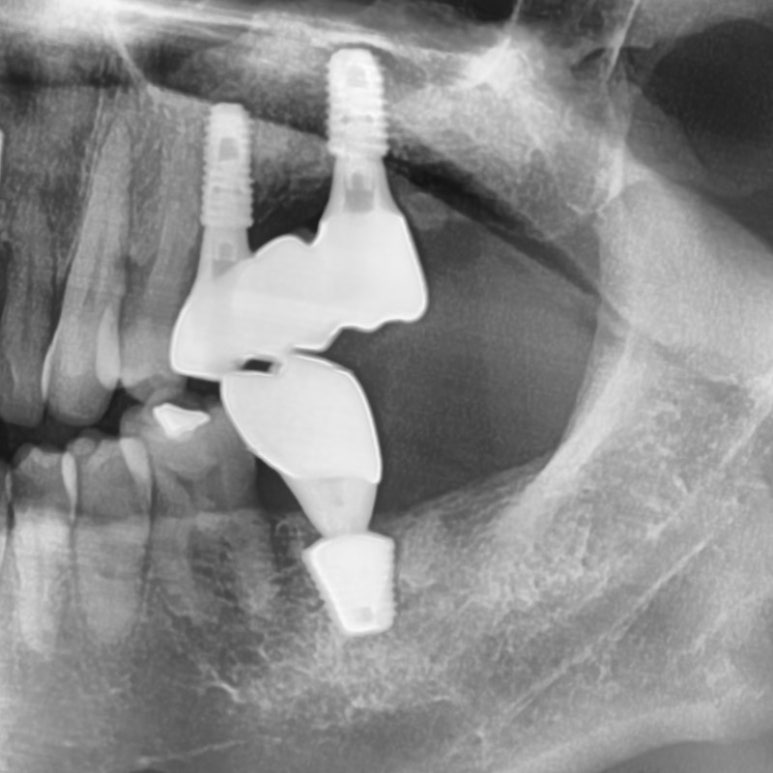

![[서울시청역치과] 다른 치과에서 오래전에 한 임플란트가 흔들려요 →재수술 케이스 관련 이미지 6](https://pub-9f2bb3498faf4d1d8714b41df24753e3.r2.dev/content/clinics/archive/rseeanjxfu/naver_blog/yonseiyegam/assets/by_hash/ea84db90f4b4850aa69afcafff7f723e6ab5ab76a91014b226204aea64acdc6b.jpg)

연결된 2개 인플란트 중

앞쪽 임플란트는 많이 흔들리는 상태였고 뒤쪽 임플란트도 반만 주변 뼈가 잡고있어 오래 못쓸거 같아

같이 빼기로 하였습니다.

또한 바로 앞의 치아도 많이 흔들려서 나중에 또 고생하느니 같이 발치하기로 하였습니다.